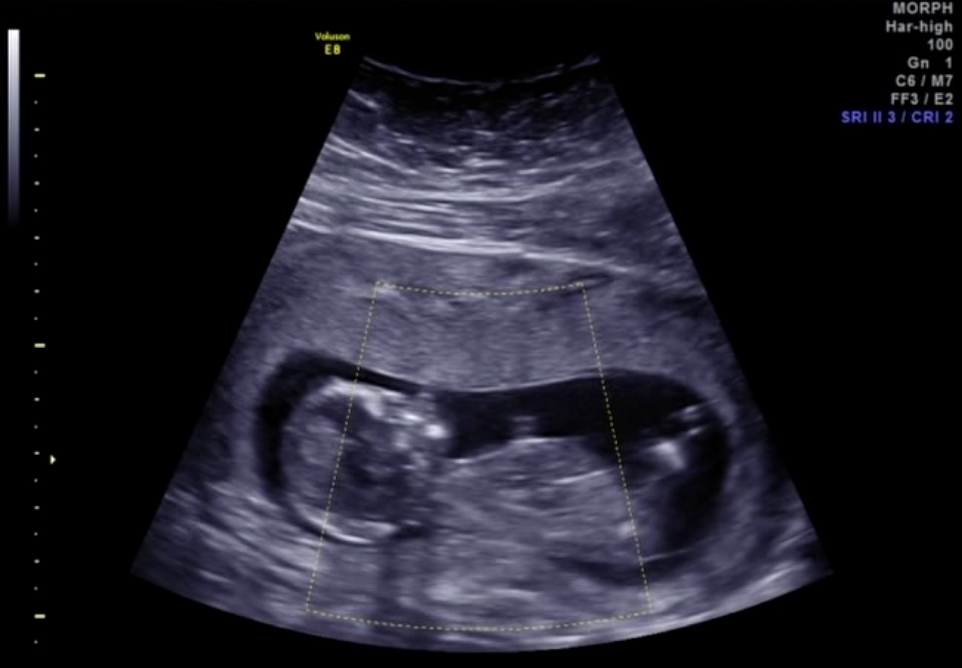

Torso/legs

Attachment 6165